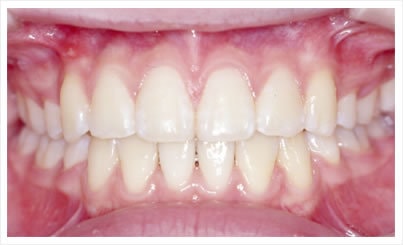

矯正による歯並びの改善

既製のものでなく、一人ひとりのお顔に合わせてワイヤーを調整します。

審美性のみでなく噛み合わせや清掃性の向上など健康面にも配慮いたします。